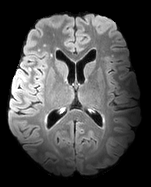

The detection of new multiple sclerosis (MS) lesions is an important marker of the evolution of the disease. The applicability of learning-based methods could automate this task efficiently. However, the lack of annotated longitudinal data with new-appearing lesions is a limiting factor for the training of robust and generalizing models. In this work, we describe a deep-learning-based pipeline addressing the challenging task of detecting and segmenting new MS lesions. First, we propose to use transfer-learning from a model trained on a segmentation task using single time-points. Therefore, we exploit knowledge from an easier task and for which more annotated datasets are available. Second, we propose a data synthesis strategy to generate realistic longitudinal time-points with new lesions using single time-point scans. In this way, we pretrain our detection model on large synthetic annotated datasets. Finally, we use a data-augmentation technique designed to simulate data diversity in MRI. By doing that, we increase the size of the available small annotated longitudinal datasets. Our ablation study showed that each contribution lead to an enhancement of the segmentation accuracy. Using the proposed pipeline, we obtained the best score for the segmentation and the detection of new MS lesions in the MSSEG2 MICCAI challenge.